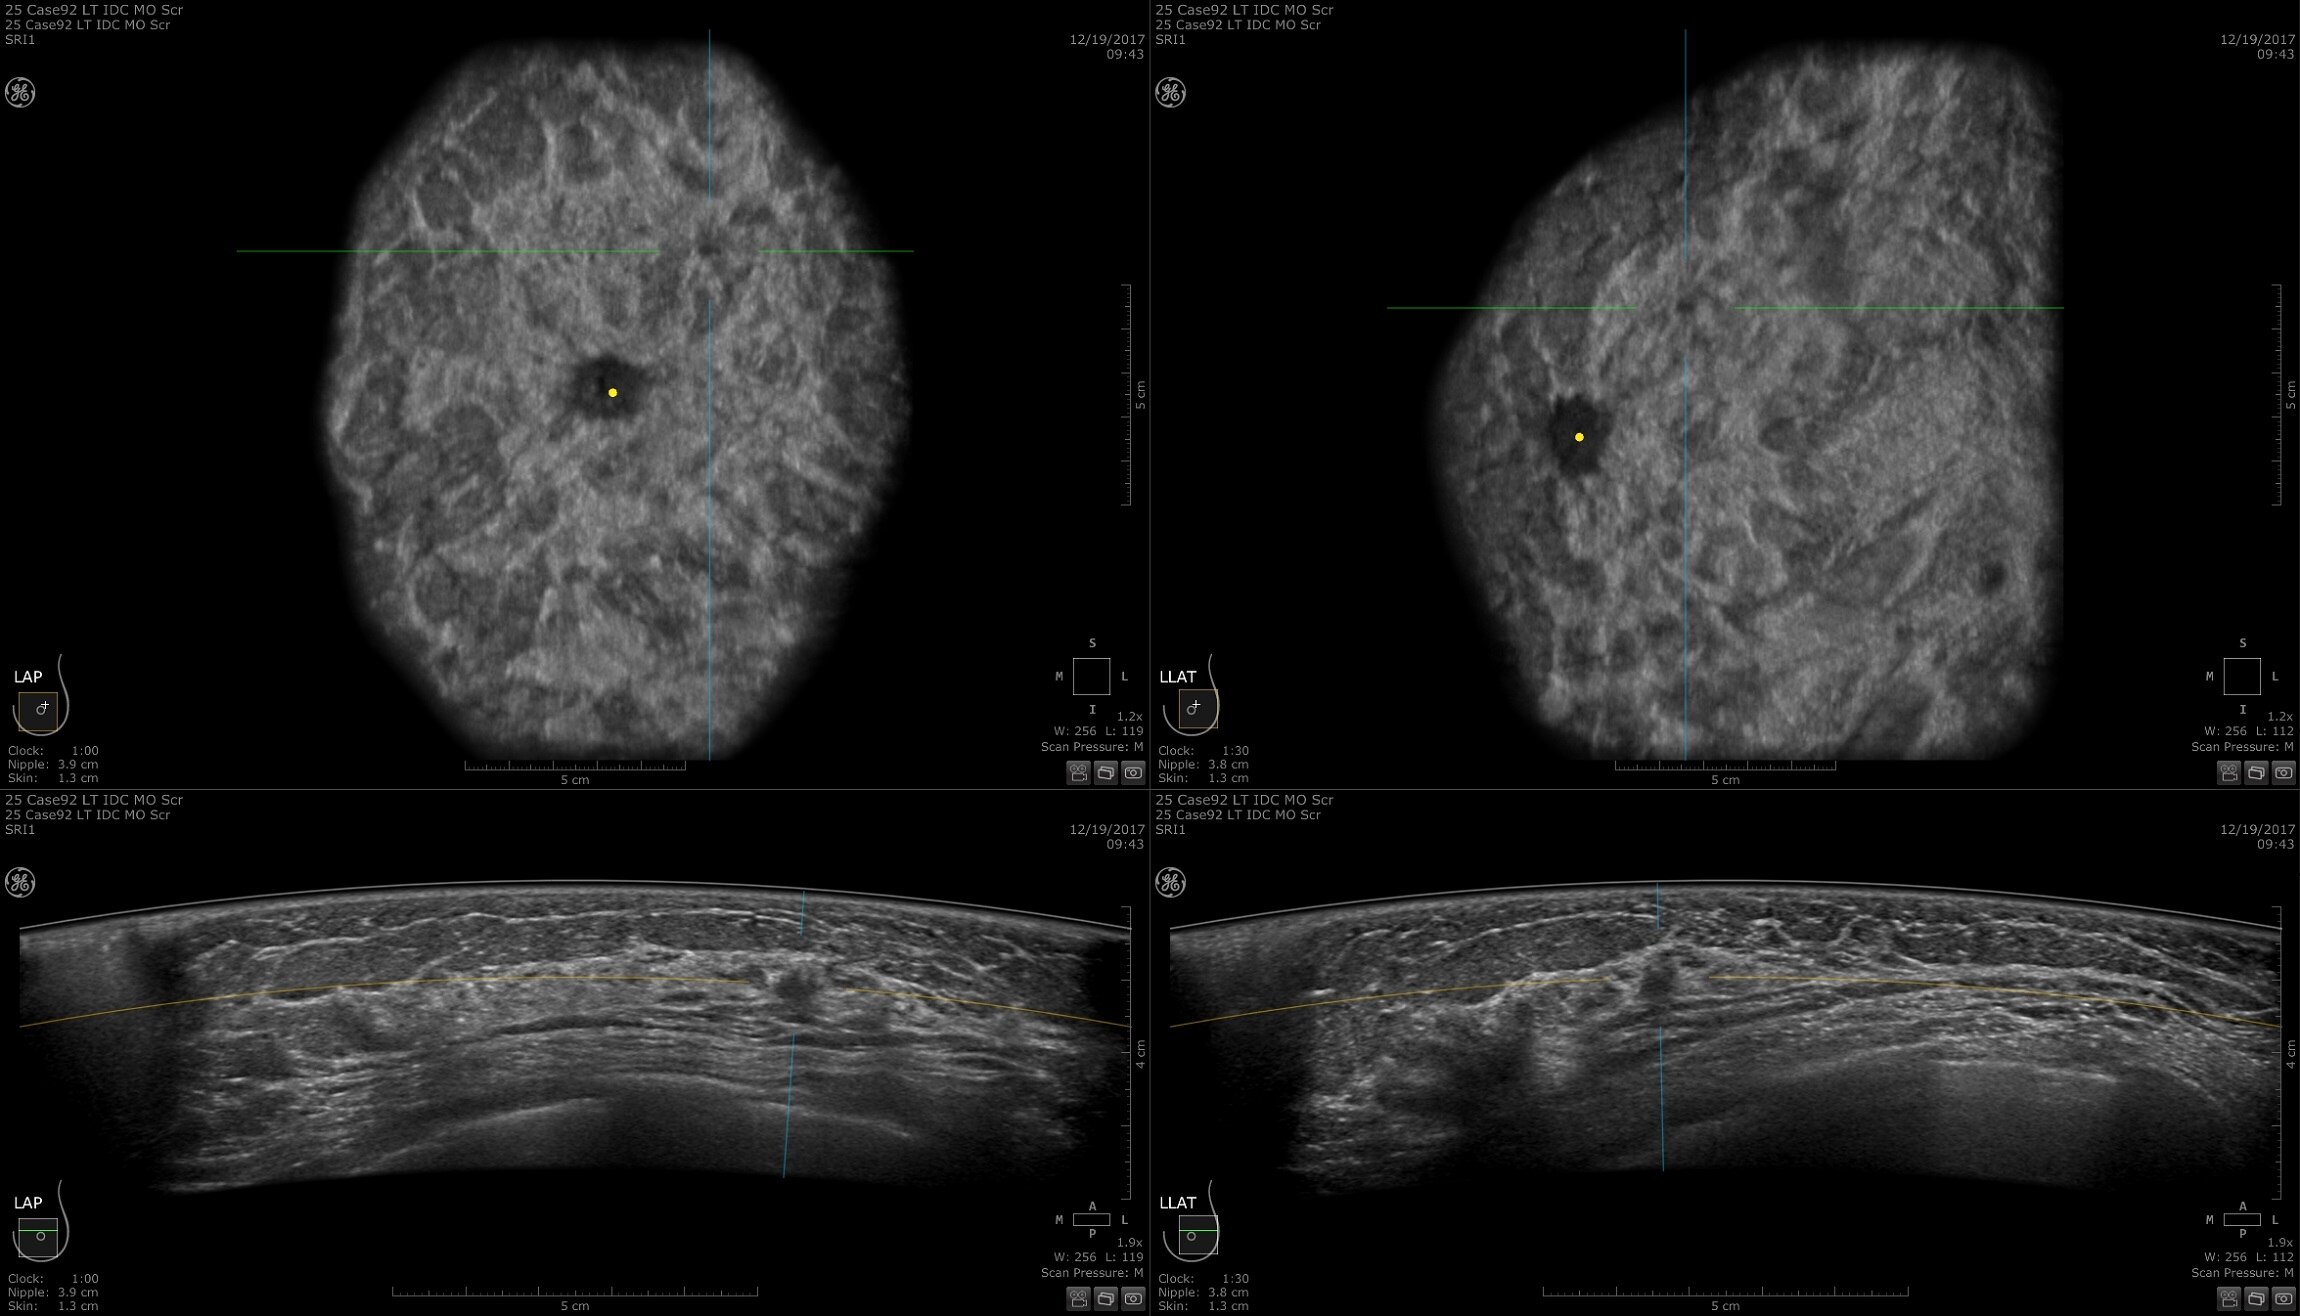

Reconstrução de imagens de RM com AIR™ Recon DL

Imagens simplesmente melhores